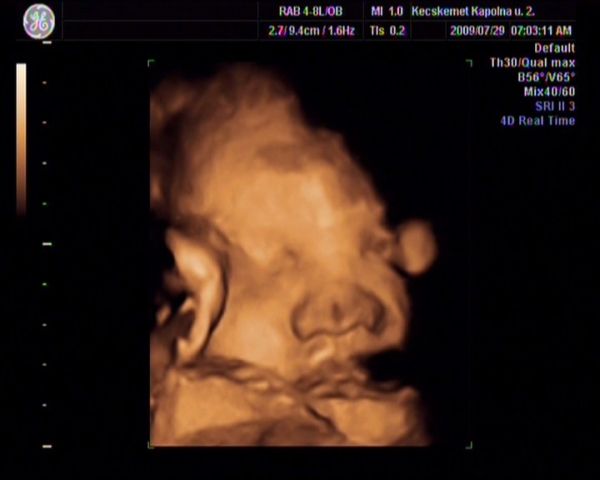

Monic: Danci mocorog már? a múlkori képet mutatva már biztos nagyon változtatja a helyeket.